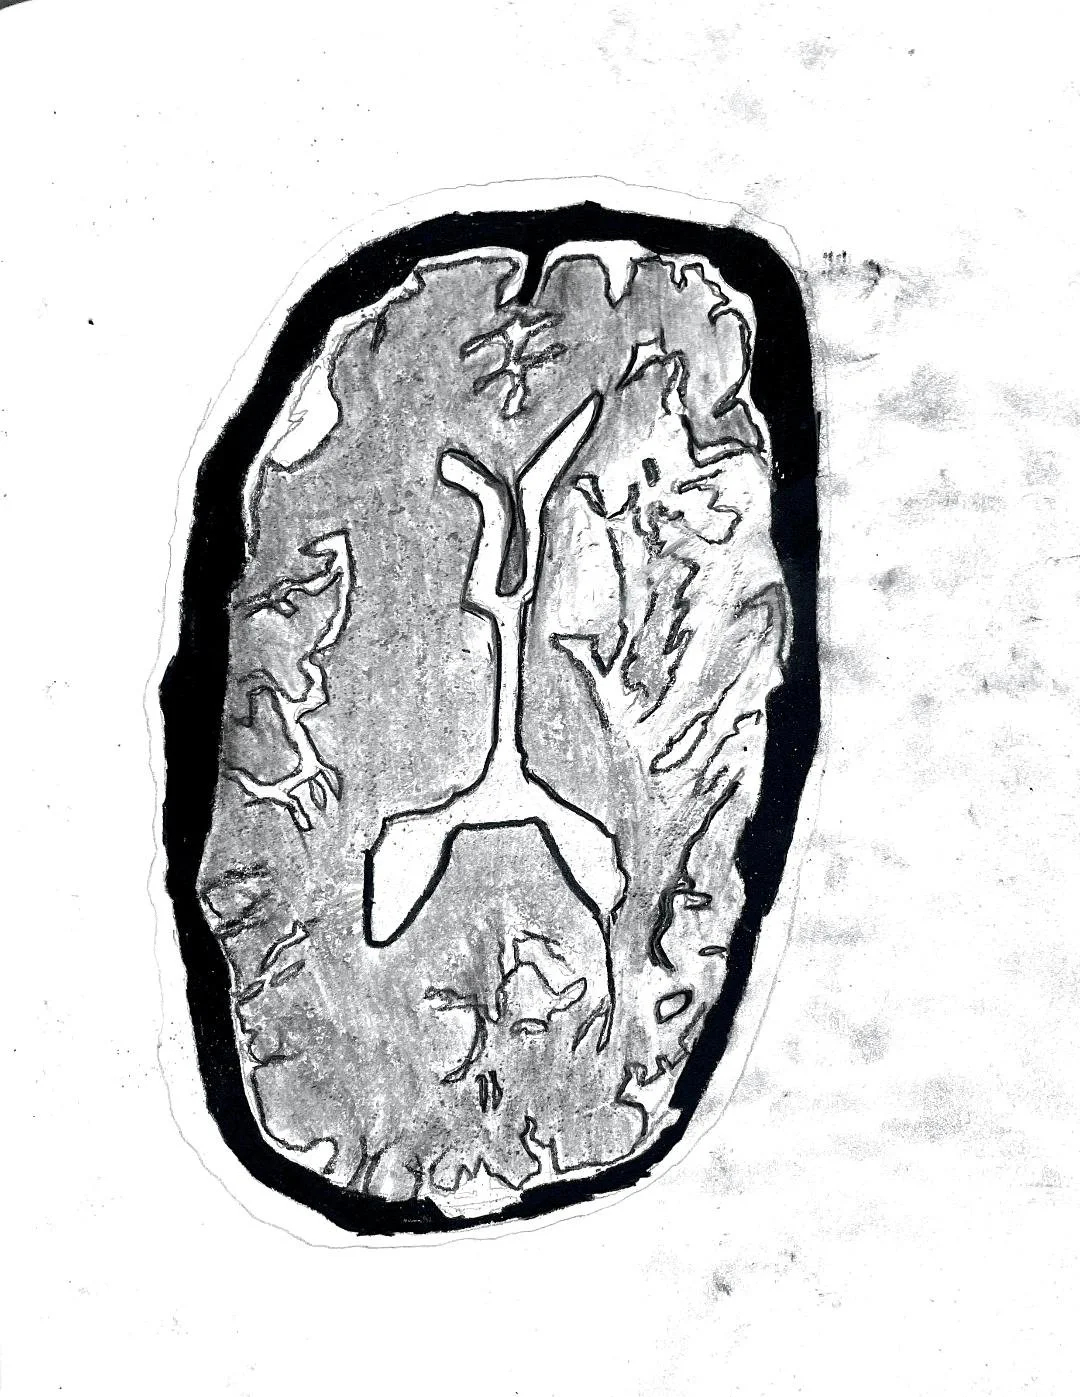

Focal cortical dysplasia

Middle cerebral artery infarction

Adult hypoxic-ischemic encephalopathy

Middle cerebral artery (MCA) infarct

Atypical PRES with acute infarct

Herpes simplex encephalitis

Mesial Temporal Sclerosis